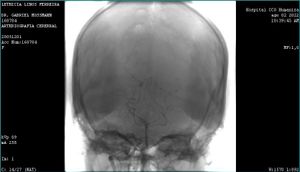

Em abril de 2022, em Porto Alegre-RS, através de um exame de ressonância magnética para investigar cefaléia, descobrimos que a nossa filha Lethícia tinha MAV, uma má formação arteriovenosa no cérebro. Em Porto Alegre realizamos diversos outros exames para a confirmação definitiva da MAV. Em maio do mesmo ano eu (pai da Lethícia) fui demitido e em julho conquistei uma vaga para trabalhar em Curitiba. A família (esposa e filhos) está separada devido essa mudança de estado, eu aqui em Curitiba e eles em Porto Alegre. Em janeiro de 2023, em Curitiba-PR, Lethícia veio para realizar novos exames no INC e atualmente já está morando definitivamente comigo provisoriamente na casa minha irmã Ana, ficando agora a esposa e o filho em Porto Alegre. Nossa família precisa se unir novamente, formar nossa família aqui em Curitiba, e por isso estamos solicitando o apoio de todos os nossos amigos, amigas, colegas de trabalho e simpatizantes com a nossa causa, assim, poderemos dar melhor atenção para o tratamento que a Lethícia deverá realizar, uma tecnologia nova e inovadora que se chama Gamma Knife, que é realizado somente no INC em Curitiba. A proposta da vaquinha é exclusiva para o custeio da nossa mudança de Porto Alegre para Curitiba, tão necessária neste momento de tratamento médico da Lethícia, por isso, qualquer contribuição será bem vinda. Agradecemos de coração antecipadamente, por sua atenção e leitura. Deus abençoe todos e todas.